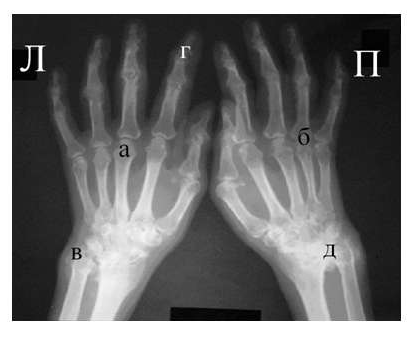

Рис. 4. Изменения кистей при ревматоидном артрите (а остеопороз, бсужение суставных щелей, в кистовидные просветвления, г костные эрозии, д анкилозирование)

Необходимо также помнить, что, как правило, при РА эрозии не предшествуют околосуставному остеопорозу, кистам и сужению суставных щелей. Имеет место последовательность развития стадий РА (см. рис. 4), в отличие от эрозивных артритов другого генеза (псориатического, серонегативного)

Костные анкилозы выявляются только в суставах запястий и во 2-5-м запястно-пястном суставах, редко в лучезапястных и суставах предплюсны. Никогда анкилозы не формируются в межфаланговых суставах кистей и стоп, в первых запястно-пястных и плюснефаланговых суставах. Анализируя сроки появления основных рентгенологических проявлений наиболее типичным по нашим данным и по данным других авторов [LandeweR.] является появление первых симптомов РА (околосуставного остеопороза и кистовидных просветлений) через несколько месяцев (до года) от начала заболевания, эрозии выявляют на 2-3 год от начала заболевания.